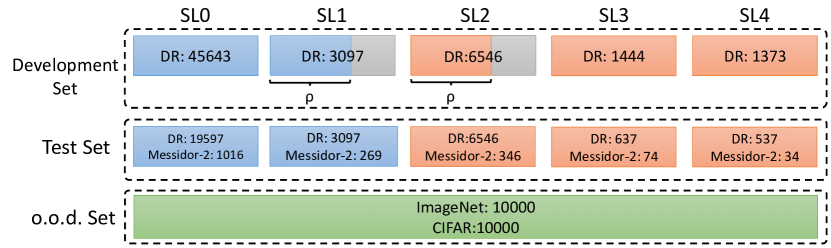

We conducted a case study on diagnosing diabetic retinopathy with ensembles of DL models. For benchmarking the performance of our ensemble-based solutions under the scheme described in Sec.3.3, we used two popular collections of diabetic retinopathy image data, the Kaggle Diabetic Retinopathy dataset [22] (hereafter referred to as “Kaggle-DR”) and the Messidor-2 dataset [23], each respectively consisting of and high resolution images. Diabetic retinopathy is graded into five SLs, as displayed in Figure 2. Following the problem setup used in previous papers [24], we trained models to distinguish the referable (SL2-4) cases from the non-referable ones (SL0 & SL1) (see Section B.1 for more detailed descriptions). We also tested our trained ensemble models on two o.o.d. image datasets (ImageNet [25] and CIFAR-10 [26]) to examine their capabilities of identifying o.o.d. inputs (see Section B in the supplementary materials).

The Kaggle-DR dataset comprises high resolution images. The presence of diabetic retinopathy is rated into five different SLs: no-DR (SL0), mild (SL1), moderate (SL2), severe (SL3), and proliferate (SL4), as illustrated in Figure 2. We divided the Kaggle-DR dataset into a development set and a test set, which respectively consisted of and images. The data in the development set were used to train and validate our Deep Learning (DL) models. The Messidor-2 dataset [38] that consisted of images was also used in our experiment as an additional dataset to test the true generalization performance of the models trained on the Kaggle-DR dataset. Images in Messidor-2 dataset were graded into the five SLs as in the Kaggle-DR dataset. Figure S.1 provides an illustration of the datasets used in our experiments.

B.2 Out-of-distribution Test Datasets: ImageNet & CIFAR-10

For comparing the performance of the evaluated ensemble methods in detecting o.o.d. data, we used ImageNet[25] and CIFAR-10[26] as additional test sets in our experiments. Due to the large sizes of these datasets, we used subsampled versions of the two image datasets by randomly selecting images from each dataset.